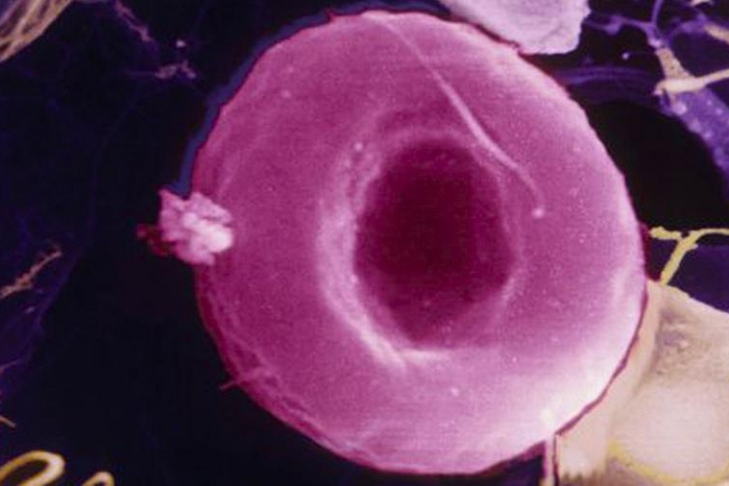

Прием митохондриально-адресованных антиоксидантов способствует омоложению кровеносных сосудов, выяснила группа ученых под руководством специалистов из Колорадского университета в Боулдере. Об этом сообщает портал MedicalXpress.

В исследовании приняли участие 20 пожилых людей в возрасте от 60 до 79 лет. Половина из них в течение шести недель употребляла антиоксидант MitoQ, действие которого нацелено на митохондрии. Остальные пациенты принимали плацебо.

Через полтора месяца оказалось, что у принимающих антиоксиданты произошли сосудистые изменения, эквивалентные омоложению на 15–20 лет. В том числе на 42% улучшилась работа сосудов.